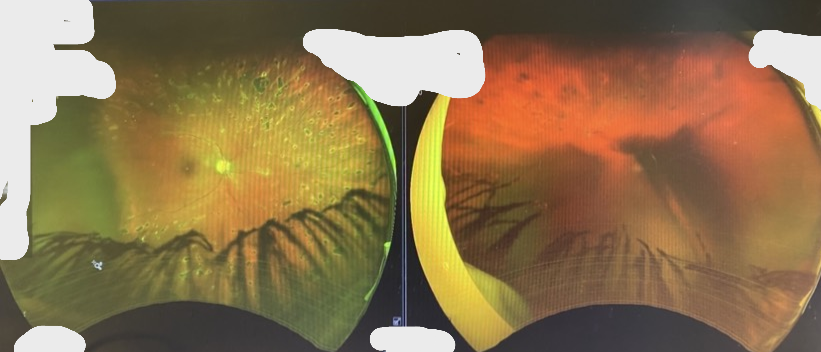

The week after my birthday, I learned there was a massive bleed in the back of my left eye and it wasn’t just “temporary.” Once the blood settled, I’d start noticing the blindness more — because ironically, I’d start seeing it.

Now, a few weeks later, I’ve learned that the gel inside my eye is slipping forward. It’s tugging at the delicate tissue attached to my retina. That tugging is causing traction that could tear or detach my retina at any moment. If that happens, there's a strong possibility of permanent damage to my vision.